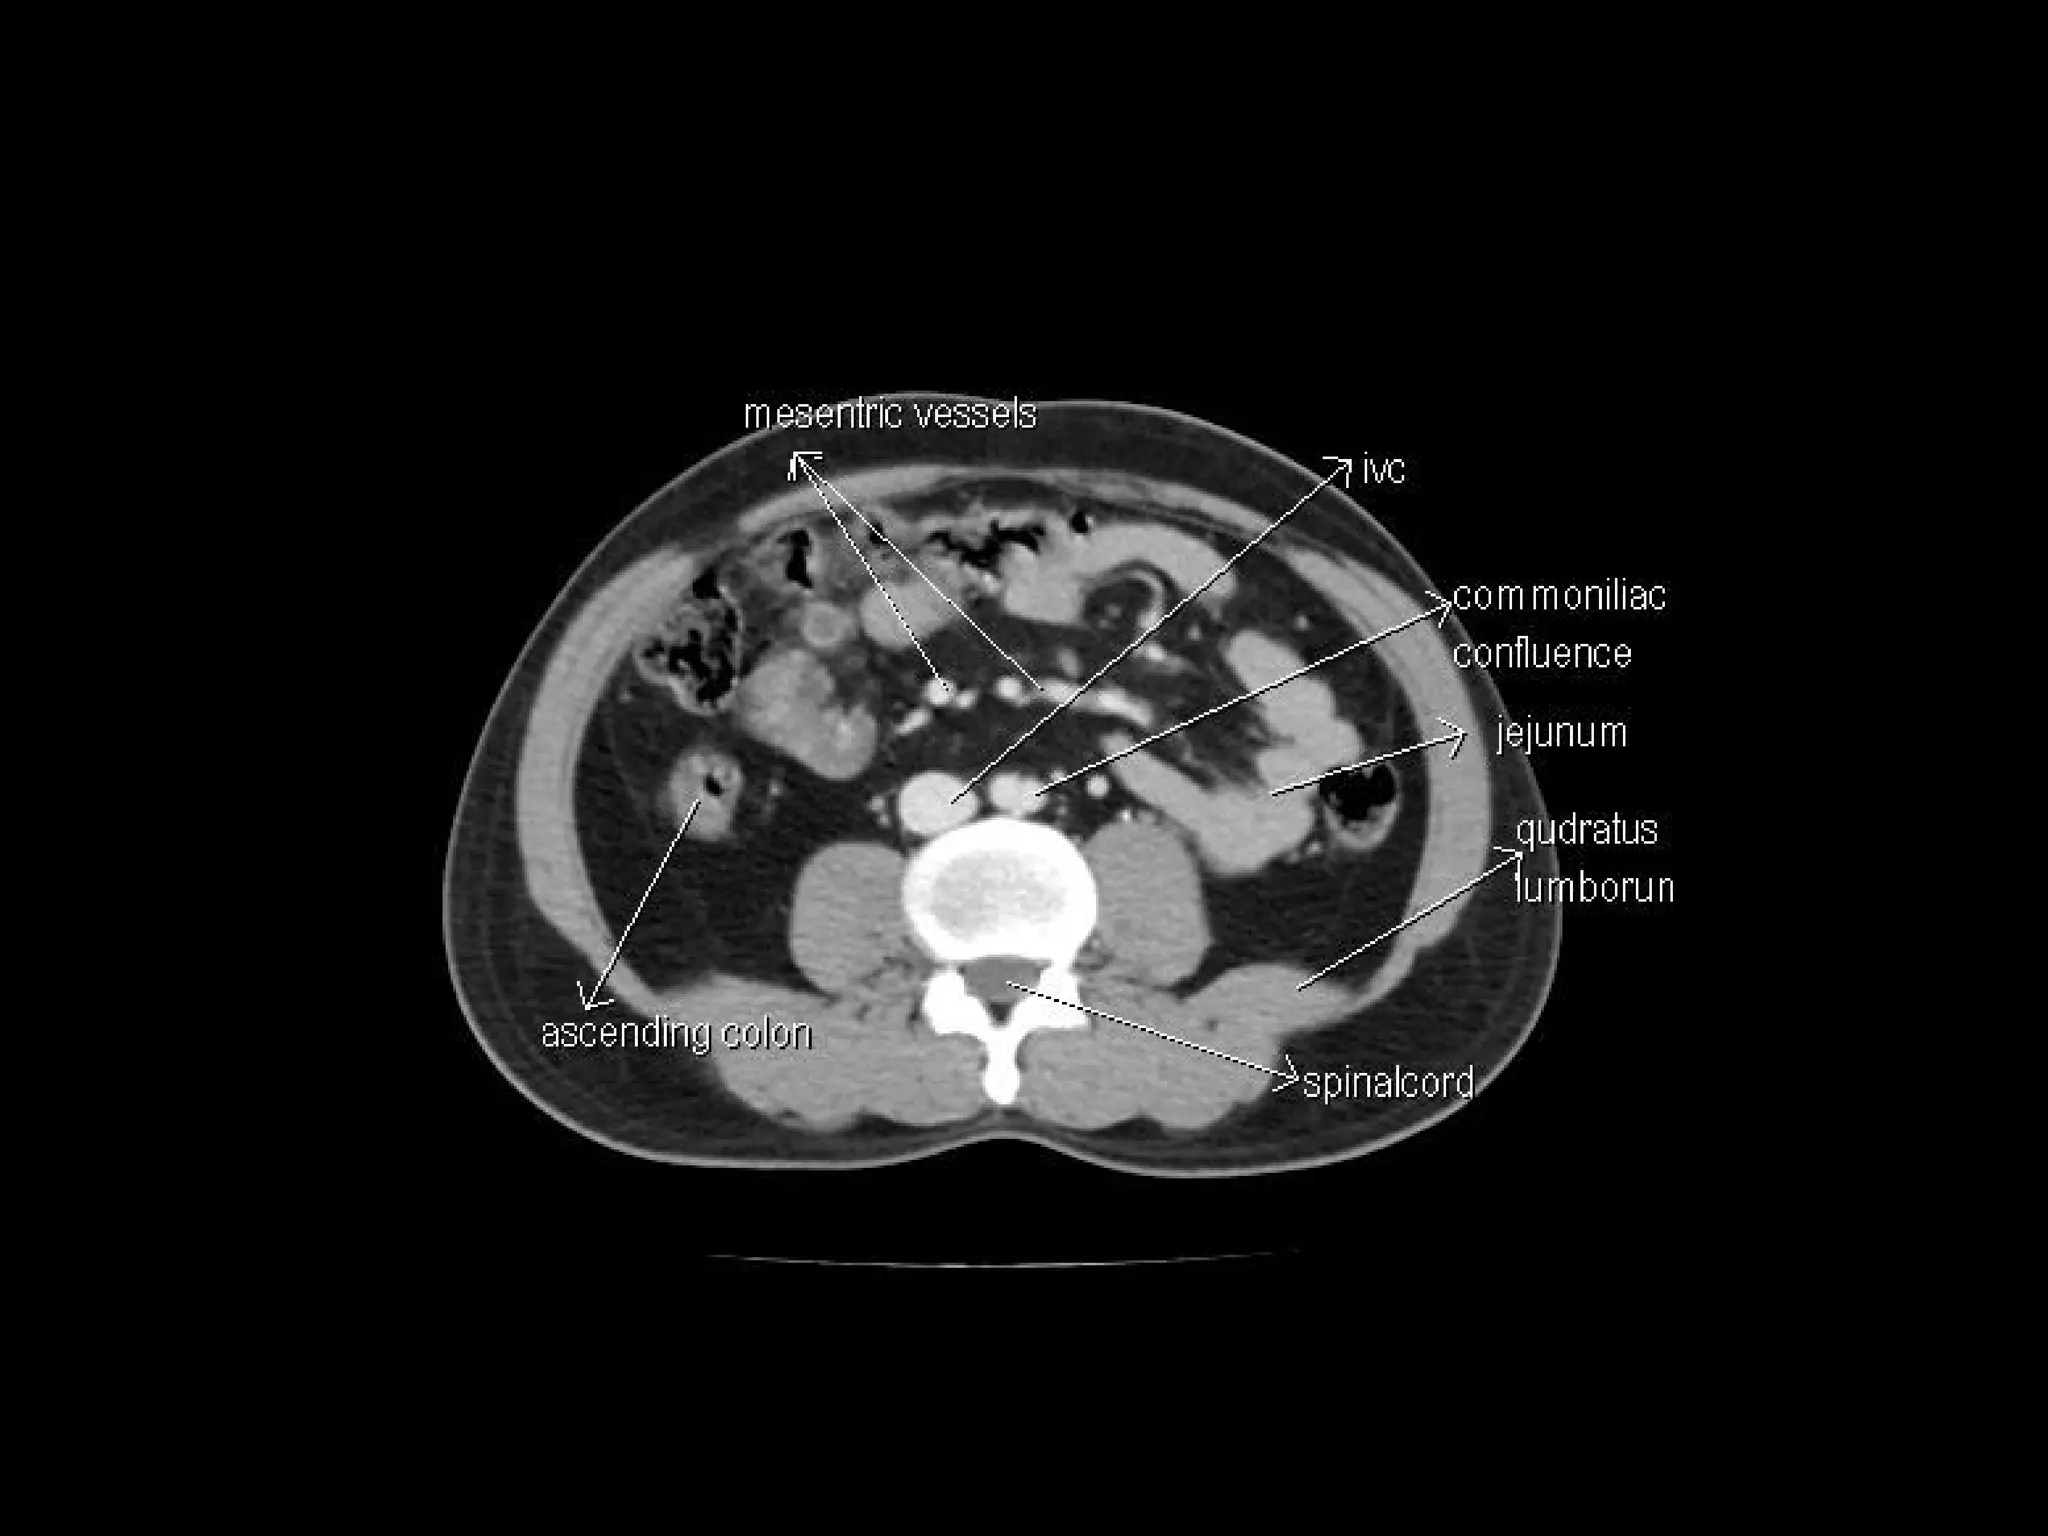

Radiographers are medical professionals who perform diagnostic imaging examinations and procedures to help physicians diagnose and treat diseases. They work under the supervision of radiologists to operate X-ray, CT, MRI, ultrasound and other medical imaging equipment and must have a strong understanding of human anatomy and pathology. Radiographers are responsible for correctly positioning patients, ensuring proper imaging techniques are used, and evaluating the quality of the resulting images.